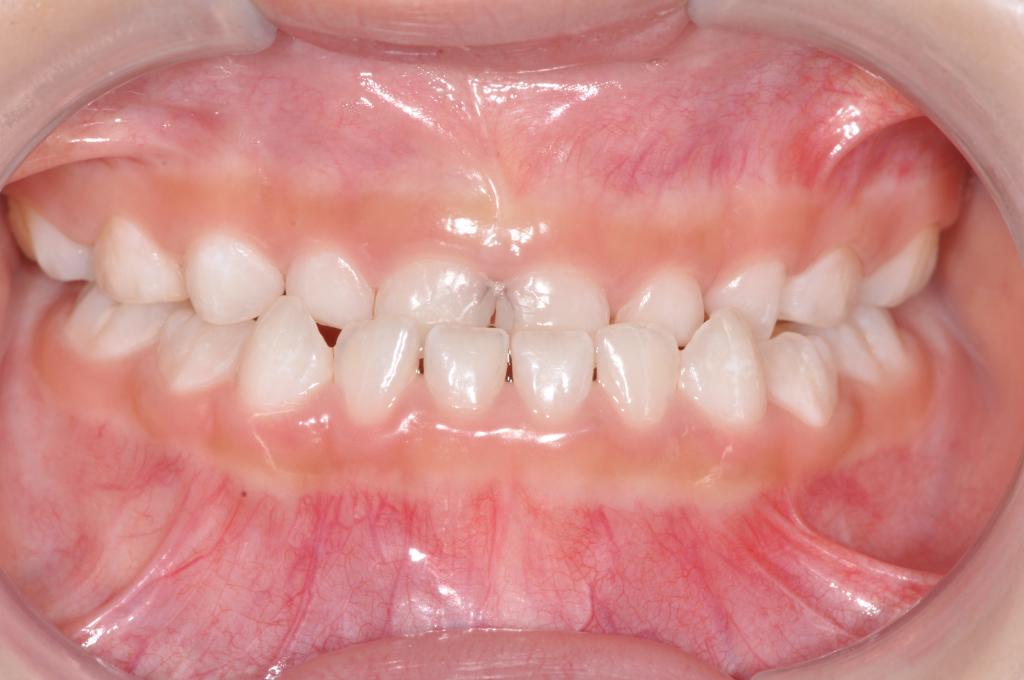

1. 前牙反合

前牙反合,俗称“地包天”,是指上下颌牙齿咬合时,下颌前牙咬在上颌前牙的外面。前牙反合随着患者的生长,症状会逐渐加重,往往造成上颌骨发育不足、下颌骨发育过度,表现为凹面型,对患者的美观、功能及心理健康均带来了极大的不良影响。乳牙列时期的前牙反合一般在3-5岁左右进行。混合牙列的前牙反合一般在8-9岁左右。

矫治方法:前牙反合的患儿往往伴有咬上唇、伸下巴、口呼吸等不良习惯。因此,应首先纠正其不良习惯。口呼吸习惯应进行耳鼻喉科会诊处理,检查其是否伴有鼻咽部疾病,排除鼻咽部疾病后,再进行纠正。对于乳牙列,常用的矫治器为合垫舌簧矫治器;对于混合牙列,常用的矫治器为前方牵引矫治器和FRⅢ矫治器。